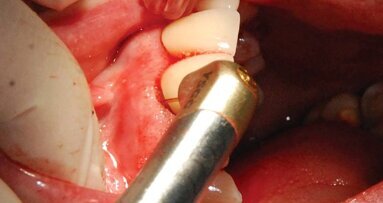

A barrier should create and maintain a sufficient space where an adequate blood supply may form to enable regeneration to occur. The space must be preserved for a certain period of time, and the barrier should be immobile during that time period. It needs to preserve this space while preventing epithelial cells and connective tissue cells from migrating into it. The barrier also must be porous so that metabolites can penetrate through to keep the underlying developing regrowth alive.

By using the GTR technique popularized by Dr. S. Nieman, we can inhibit the causal factors of this periodontal disease and support proper cellular regeneration. This technique involves forming a porous barrier membrane that excludes the undesired cells, yet allows nutriment through its porous membrane to aid the selective population by undifferentiated mesenchymal cells toward the regenerative goal.

This case describes two areas of recession in a single mouth, thus influenced by identical saliva and oral habits. I used the same cosmetic surgery technique on both areas but used a barrier on only one of the areas (Figs. 3–6).

The 10-plus year outcome (Fig. 7) shows complete root coverage of gingiva on tooth #11, where the barrier collagen TranZgraft was used. The adjacent bicuspid #12 had the same coronal repositioned gingival flap procedure at the same time but without use of the connective tissue barrier.